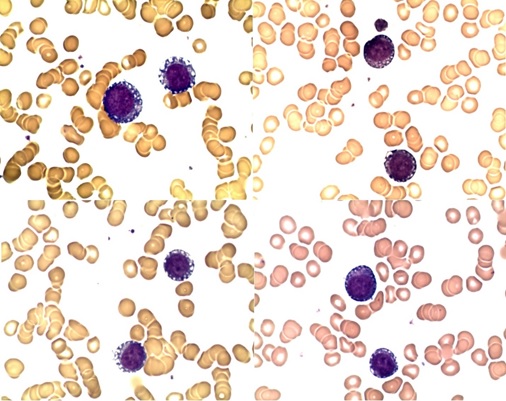

A Case Report of Acute Myeloid Leukemia in a Patient Treated with Pembrolizumab